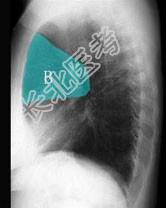

- 单项选择题在图所示正常胸部X线影像图像上,该英文字母所代表的肺段为 ( )

A、尖段

B、后段

C、尖后段

D、舌叶上段

E、前段